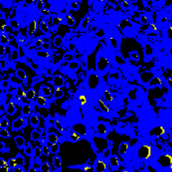

Figure 1: (a) H&E stained image; (b) H-component; (c) E-component; (d) fully annotated label; (e) Voronoi label; (f) cluster label; (g) inaccurate and incomplete area of (e) and (f), compared with (d). In (e) and (f), the green, red, and black pixels denote the label of positive, negative and ignored area, respectively. In (g), the yellow and blue masks denote the inaccurate and incomplete area, respectively.

Point annotation can be viewed as the most efficient manner for annotation, gaining increasing attention in cell/nuclei segmentation. Existing methods [23, 24, 25, 26] mainly encode the point annotation into coarse pixel-level labels, such as point distance maps [23], Voronoi labels [24], cluster labels [25], and pseudo edge maps [26]. As shown in Fig. 1, these methods typically inject the shape and texture prior knowledge of nuclei into coarse pixel-level label. For example, the points are assumed to be around the center and the nuclei shapes are nearly convex. Despite drastically reducing the annotation cost and alleviating the data-imbalance problem of point annotation, these methods still suffer from incomplete coarse labels and inaccurate boundary information, as illustrated in Fig. 1. Various methods have been proposed to eliminate the distraction induced by the coarse labels, which can be categorized into two classes: 1) multi-stage optimization to refine the segmentation in a bootstrapping way [23, 27, 24]; 2) adding additional constraints based on the local contrast between nuclei and their surrounding cytoplasm [25, 26]. However, the additional constraints could introduce inaccurate supervision, and a multi-stage learning strategy may suffer from error accumulation (i.e., the global optimum cannot be guaranteed).

In practice, directly using point annotation for the nuclei segmentation could suffer from the data-imbalance problem due to insufficient supervision information. To alleviate this issue, we adopt the Voronoi diagram [24] and the k𝑘k-means clustering method [25] to generate Voronoi label and cluster label, respectively. Specifically, for Voronoi labels, as shown in Fig. 1, the image is divided into convex polygons based on the point annotations with the assumptions that the point labels are at the nuclei centers and nuclear shapes are convex (even though these assumptions are not necessarily valid). For cluster labels, as shown in Fig. 1, we utilize the k𝑘k-means to obtain more supervision information of nuclei boundary and shape as follows. First, we calculate the distance maps from the point labels by performing distance transform between each pair of points. Second, the distance maps are combined with the original H&E stained images to conduct the k𝑘k-means clustering to divide all pixels into k=3𝑘3k=3 clusters: nuclei, background, and ignored area. The clusters that have maximum and minimum overlap with the point annotations are labeled as nuclei and background, respectively. The remaining one is the ignored class. The introduction of an ignored area allows pixels that cannot be easily determined as nuclei or background with certainty not be forced into either class, ensuring that the clustering can assign correct pixel labels as much as possible [27]. Third, several morphological operations are adopted to refine the cluster label, including connected domain labeling, scattered region removing, morphological opening operation, and binary hole filling.

where visubscript𝑣𝑖v_{i} and cisubscript𝑐𝑖c_{i} denote the Voronoi label and cluster label of nuclei at the i𝑖i-th pixel, respectively; y=S(xh)𝑦𝑆subscript𝑥y=S(x_{h}) denotes the prediction of the segmentation network S𝑆S with H-component xhsubscript𝑥x_{h} as input; and ΩsubscriptΩ\Omega_{*} (i.e., ΩvsubscriptΩ𝑣\Omega_{v} or ΩcsubscriptΩ𝑐\Omega_{c}) is the set of non-ignored pixels. As illustrated in Fig. 1, the Voronoi label is used to supervise the network to separate overlapping nuclei, while the cluster label could provide coarse shape and boundary information for nuclei segmentation. In the following, we elaborate the co-training strategy to further provide supervision to the ignored area of the coarse cluster labels, denoted with the blue color in Fig. 1.

where pisubscript𝑝𝑖p_{i} is the i𝑖i-th pixel of the pseudo label, ΩΩ\Omega is the set of all pixels, and ya=Sa((xh)a)subscript𝑦𝑎subscript𝑆𝑎subscriptsubscript𝑥𝑎y_{a}=S_{a}((x_{h})_{a}) denotes the predictions of Sasubscript𝑆𝑎S_{a} with respect to the H-component (xh)asubscriptsubscript𝑥𝑎(x_{h})_{a}. With the training set X𝑋X split into two non-overlapping subsets Xasubscript𝑋𝑎X_{a} and Xbsubscript𝑋𝑏X_{b}, two segmentation networks are trained with the coarse labels (i.e., the Voronoi and cluster labels) by Xasubscript𝑋𝑎X_{a} and Xbsubscript𝑋𝑏X_{b}, respectively, the two networks could transfer knowledge to each other with their respective pseudo labels, so as to compensate for the missing supervision information. However, the segmentation performance may still suffer from the inaccurate cluster label, as shown in Fig. 1. Hence, our next step is to explore an auxiliary colorization task that transforms H-component images back into the original H&E stained images from which more precise nuclei boundaries can be obtained.